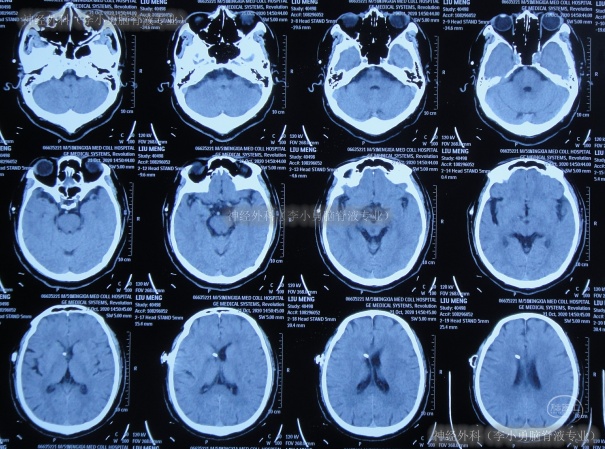

但出院后1个月即2020年12月6日(脑室腹腔分流术后3年零2月),再次出现嗜睡,第3次就诊该院,查头颅CT(片子丢失)后认为脑室系统与1月前相比并未明显扩张,但第2天即2020年12月7日,出现昏迷,大小便失禁,再查头颅CT(图-3)后认为脑室有大。

图-3:2020年12月7日头颅CT